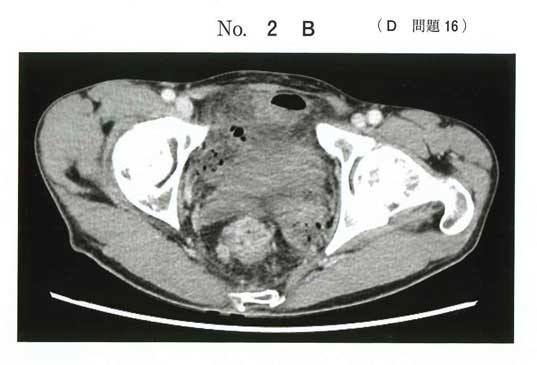

画像と所見から直腸癌で、開腹による直腸手術を行う。

直腸手術では肛門操作・骨盤内操作が必要なため、砕石位が基本。